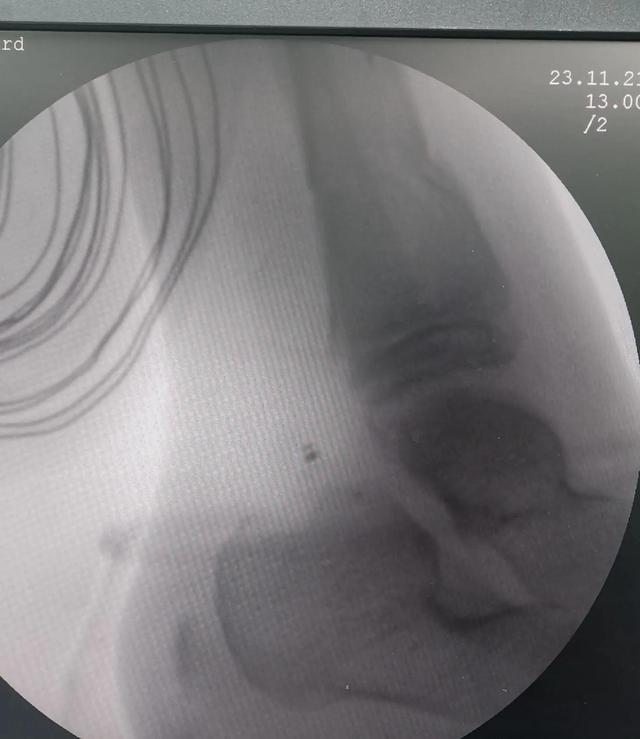

我们治疗了一个车祸后住院2小时的孩子。

术前侧卧位显示后屈畸形矫正至10.87度,不符合复位要求。

手动缩减后的审查

术中透视下闭合复位,跖屈及后屈畸形完全矫正。

术中闭合复位